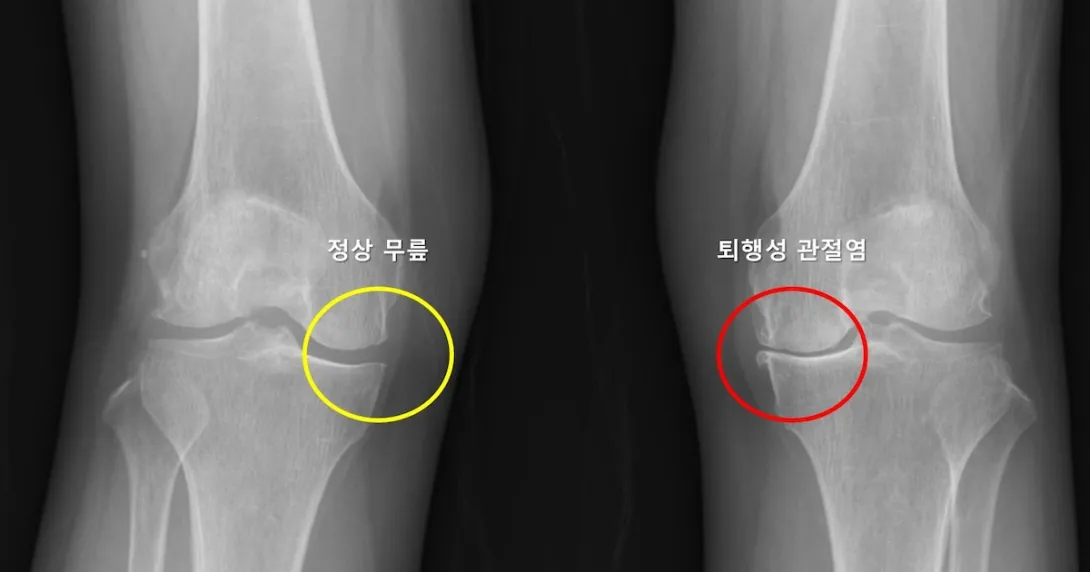

Photo courtesy of Seoul National University Hospital

Researchers from Seoul National University Hospital (SNUH) have developed an AI model for predicting the likelihood that patients with unilateral osteoarthritis would develop the same condition in their other knee.

A major finding of the study, published in Wiley's Journal of Orthopaedic Research, was that a reduction in the lateral joint space of the contralateral knee is a major risk factor for osteoarthritis of the contralateral knee, increasing the risk by 4.5 times.

The study also demonstrated for the first time that the severity of arthritis and the pain and function index of the unilateral knee arthritis are greatly associated with the development of osteoarthritis in the opposite knee.

Additionally, the model demonstrated 69% accuracy in identifying patients with a high risk of developing contralateral knee arthritis.